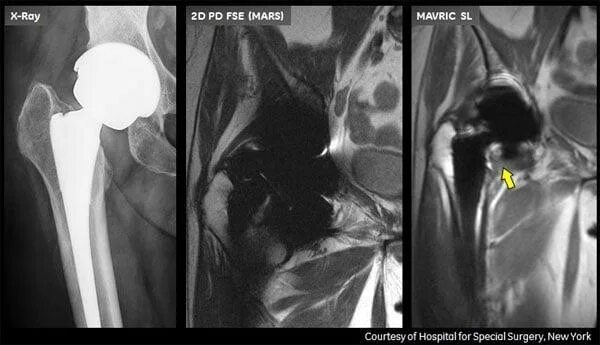

Можно ли эндопротезом делать мрт